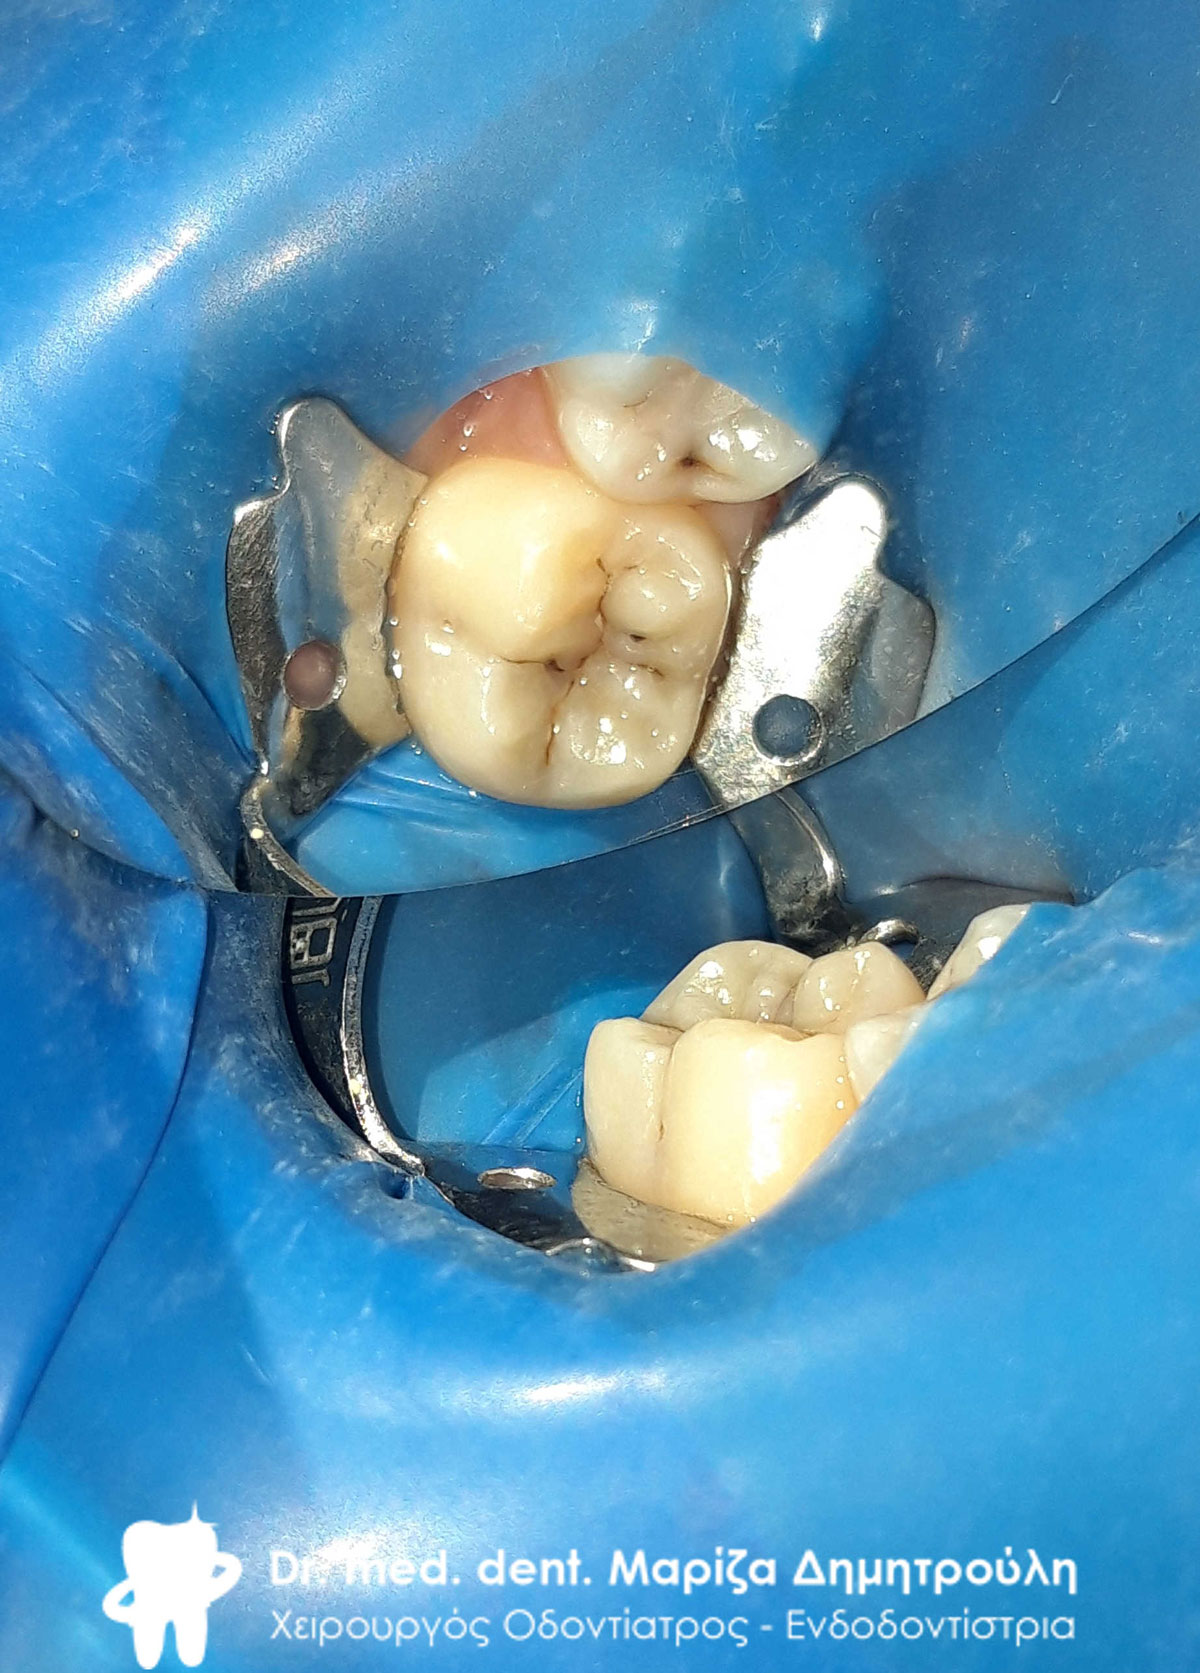

Η μικρή ασθενής επισκέφτηκε το ιατρείο με σκοπό την αποκατάσταση του στόματος της, το οποίο είχε πολλές τερηδονικές αλλοιώσεις. Ένα πίσω δόντι της στην αριστερή πλευρά της άνω γνάθου ήταν τόσο κατεστραμμένο, ώστε στο στόμα της είχαν απομείνει μόνο οι σάπιες ρίζες του δοντιού.

Αξίζει να σημειωθεί οτι τα περισσότερα σφραγίσματα στην ασθενή πραγματοποιήθηκαν με τη μέθοδο stamp technique, ώστε η μορφολογία ων τελικών σφραγισμάτων να μοιάζει όσο το δυνατόν περισσότερο με τα φυσικά δόντια της ασθενούς.

Μετά την εξαγωγή του δοντιού, την απονεύρωση στον κεντρικό τομέα της και τα λευκά σφραγίσματα που πραγματοποιήθηκαν στο στόμα της η ασθενής κατέχει ένα υγιές και λαμπερό όμορφο χαμόγελο.